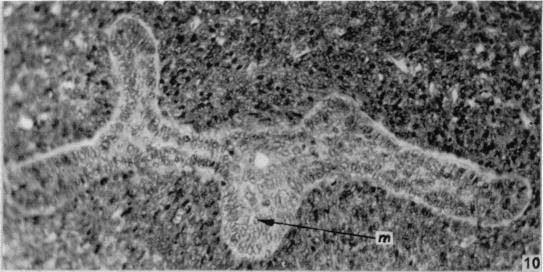

The development of the human vagina.

J Anat. 1957 Oct;91(4):490-509.